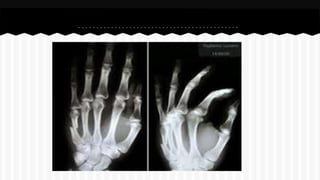

RESPONDA O NOME DO OSSO EM QUE

SE ENCONTRA A (S) FRATURA (A).